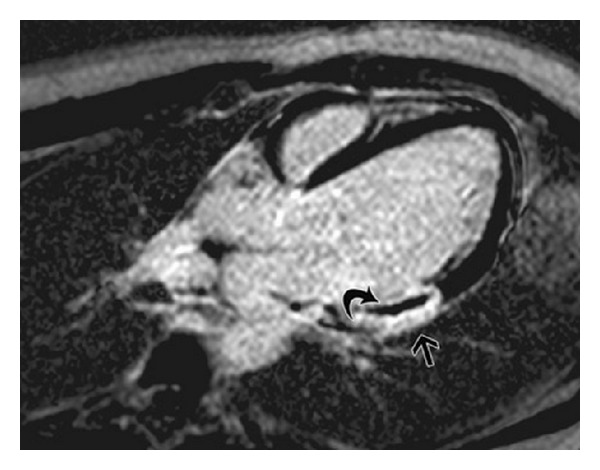

目标先前的研究表明,在st段抬高型心肌梗死(STEMI)患者中,静脉给药腺苷可改善心肌再灌注并减小梗死面积。冠状动脉内给药腺苷显示了相互矛盾的结果。方法。在这项回顾性、单中心、盲法临床研究中,我们通过心脏磁共振成像(MRI)评估了在初始球囊膨胀前立即在闭塞部位远端冠状动脉内选择性给药腺苷是否能减少微血管阻塞(MVO)。利用对比增强序列,计算微血管阻塞(MVO)。我们发现81例在症状出现后12小时内出现STEMI的患者符合研究条件。在80/81(100%)接受研究药物的患者中,在初次血管成形术后第1天进行MRI检查。结果。冠脉内注射腺苷组的MVO患病率降低了45%,而静脉注射腺苷组的MVO患病率为85% (P = 0.0043)。我们发现,与静脉注射组的0.91 g相比,接受冠状动脉内腺苷治疗的患者的MVO大小明显减少(P = 0.027)。初次PCI后TIMI流量及临床结果无统计学差异。结论。我们发现有重要证据表明,STEMI患者在罪魁祸首病变闭塞部位远端冠状动脉内选择性高剂量给药腺苷可减少微血管阻塞。

Aims. Previous studies have suggested that intravenous administration of adenosine improves myocardial reperfusion and reduces infarct size in ST-elevation myocardial infarction (STEMI) patients. Intracoronary administration of adenosine has shown conflicting results. Methods. In this retrospective, single-centre, blinded clinical study, we assessed whether selective intracoronary administration of adenosine distal to the occlusion site immediately before initial balloon inflation reduces microvascular obstruction (MVO) as assessed with cardiac magnetic resonance imaging (MRI). Using contrast-enhanced sequences, microvascular obstruction (MVO) was calculated. We found 81 patients presenting with STEMI within 12 h from symptom onset who were eligible for the study. In 80/81 (100%) patients receiving the study drug, MRI was performed on Day 1 after primary angioplasty. Results. The prevalence of MVO was reduced in the patients treated with intracoronary adenosine, (45%) compared to 85% of patients who were administered intravenous adenosine (P = 0.0043). We found that the size of MVO in patients receiving intracoronary adenosine was significantly reduced compared to 0.91 g in the intravenous-treated group (P = 0.027). There was no statistically significant difference in TIMI flow and clinical outcomes after primary PCI. Conclusion. We found significant evidence that selective high-dose intracoronary administration of adenosine distal to the occlusion site of the culprit lesion in STEMI patients results in a decrease in microvascular obstruction.